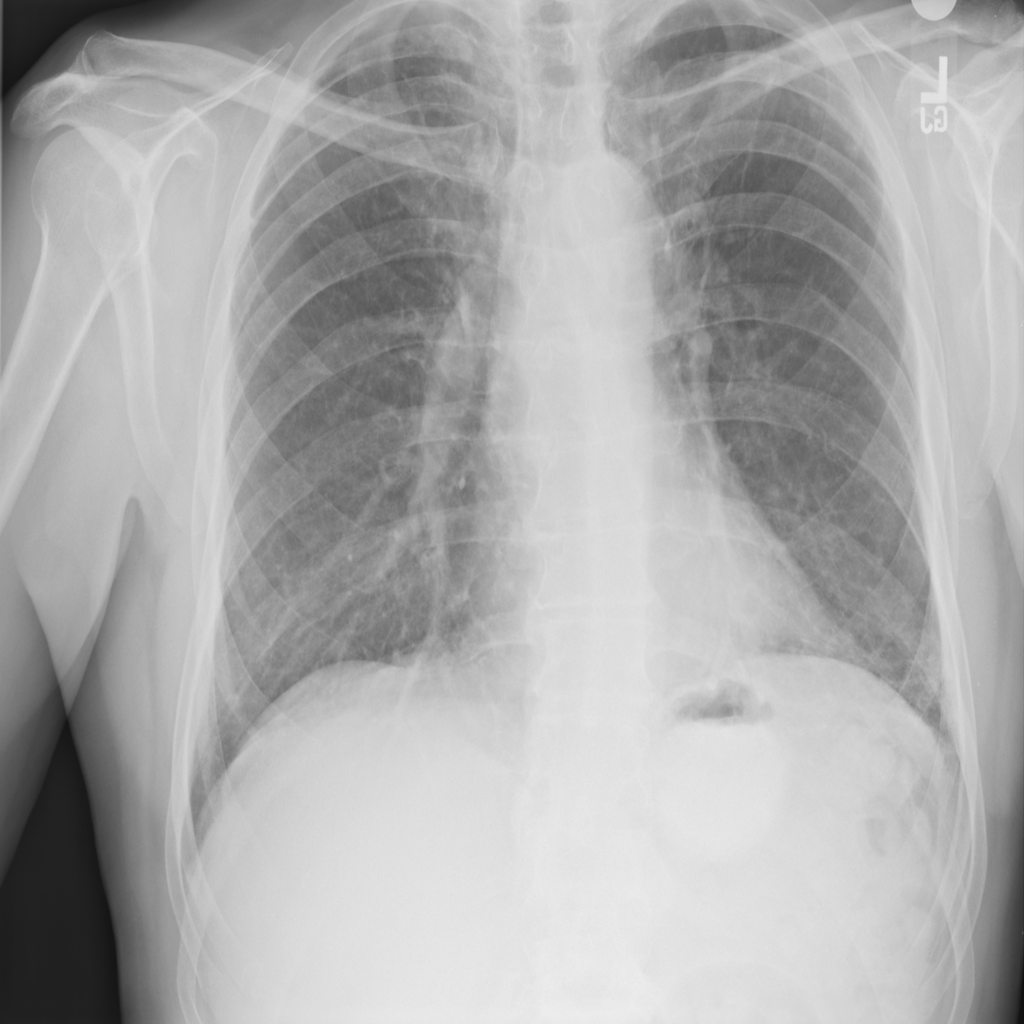

Nodule

A nodule is a small rounded opacity in the lung or chest field. It is a descriptive imaging finding that can be benign or more concerning depending on size, appearance, and context.

Showing up to 90 reference images for Nodule.